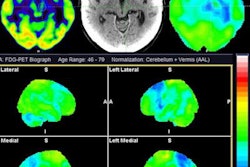

Visualization of average saliency maps of patients with idiopathic Parkinson's disease (IPD), multiple system atrophy (MSA), and progressive supranuclear palsy (PSP) in the training cohort showing characteristic regions contributing to the deep metabolic imaging (DMI) indices. The color corresponds to the importance score indicating the contribution of a region for the generated DMI indices. The color directions (yellow and red vs. cyan and blue) represent different influences on the DMI indices (increased uptake value contributes to the increase or decrease of the probability of IPD, MSA, or PSP in the DMI indices). The arrows pointed to the most salient brain regions including 1: Cerebellum, 2: Midbrain, 3: Putamen, and 4: Thalamus. Image courtesy of the Journal of Nuclear Medicine.

Visualization of average saliency maps of patients with idiopathic Parkinson's disease (IPD), multiple system atrophy (MSA), and progressive supranuclear palsy (PSP) in the training cohort showing characteristic regions contributing to the deep metabolic imaging (DMI) indices. The color corresponds to the importance score indicating the contribution of a region for the generated DMI indices. The color directions (yellow and red vs. cyan and blue) represent different influences on the DMI indices (increased uptake value contributes to the increase or decrease of the probability of IPD, MSA, or PSP in the DMI indices). The arrows pointed to the most salient brain regions including 1: Cerebellum, 2: Midbrain, 3: Putamen, and 4: Thalamus. Image courtesy of the Journal of Nuclear Medicine.The deep metabolic imaging indices extracted from PDD-Net provided an early and accurate method for the differential diagnosis of parkinsonian syndromes, with high rates of sensitivity and specificity for Parkinson's disease, multiple system atrophy, and progressive supranuclear palsy, according to the findings.